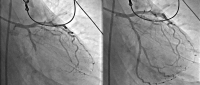

Koronarmorphologie

Abbildung 4: Darstellung der Koronarmorphologie der linken Koronararterie. Im linken Bild zeigt sich der Ramus circumflexus verschlossen. Im rechten Bild kommt nach der akuten Revaskularisation distal der Verschlussstelle eine Bifurkation zur Darstellung, deren Äste sowohl antero- als auch posterolaterale Areale des linken Ventrikels versorgen.